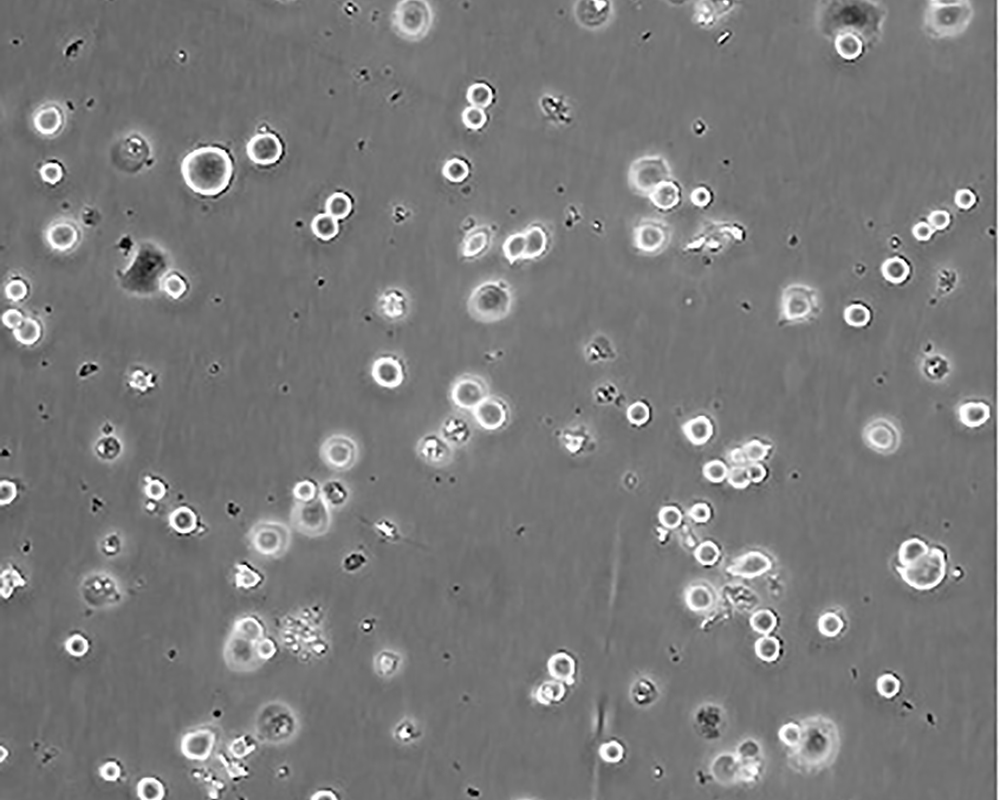

生長特性 adherent

形態特征 epithelial

細胞描述 he patient, a White, Caucasian female, age 43, blood type A+, had been treated with radiation, steroids, cytoxan and 5-fluorouracil.No virus particles.Ultrastructural features include microvilli and desmosomes, glycogen granules, large lysosomes, bundles of cytoplasmic fibrils.The SKBR- 3 cell line overexpresses the HER2/c-erb-2 gene product.